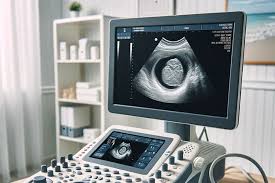

سونوگرافی پروستات؛ روش مطمئن برای بررسی سلامت آقایان

سونوگرافی پروستات یکی از روشهای تصویربرداری پزشکی است که برای بررسی و ارزیابی پروستات به کار میرود. پروستات یک غده کوچک است که در زیر مثانه مردان قرار دارد و نقش مهمی در تولید مایع منی دارد. این آزمون غیرتهاجمی و بدون درد است و از امواج صوتی با فرکانس بالا برای تولید تصاویر دقیق از ساختار پروستات استفاده میکند.

• در این روش یک پروب کوچک به داخل مقعد وارد میشود و امواج صوتی با فرکانس بالا به پروستات ارسال میشود. این امواج بازتاب یافته و تصاویر دقیقی را از ساختار پروستات تولید میکنند. این روش که به اختصار TRUS نامیده میشود، معمولاً برای تشخیص سرطان پروستات و بزرگی خوشخیم پروستات (BPH) و التهاب پروستات (پروستاتیت) به کار میرود.

در این روش پروب سونوگرافی بر روی سطح شکم قرار میگیرد و امواج صوتی از طریق دیواره شکم به پروستات ارسال میشوند. این روش غیرتهاجمی است و معمولاً برای بررسی اندازه پروستات در مواردی که TRUS مناسب نیست، استفاده میشود.